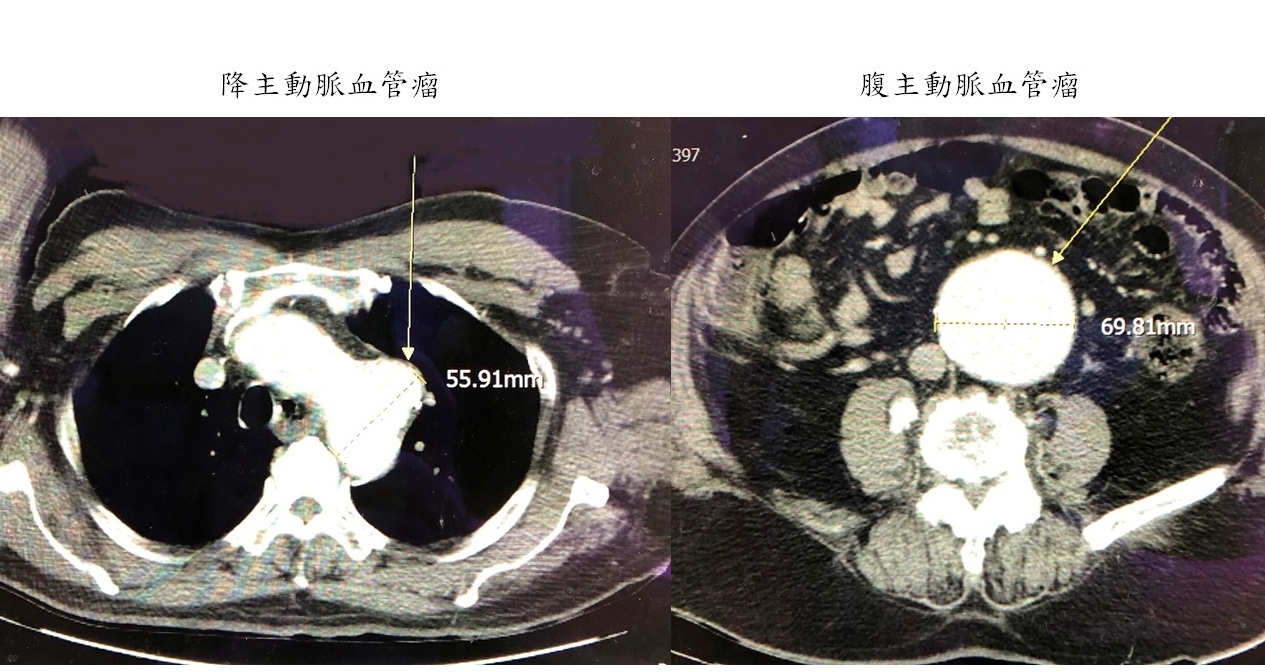

一位85歲的老先生因為出現劇烈背痛後昏厥而送至醫院急診,經檢查後發現,在降主動脈的近端發現一個5.6公分的血管瘤,且在腹主動脈上也發現一個6.9公分的血管瘤,由於兩個血管瘤都相當大,隨時有破裂的風險,才會導致病人產生劇烈疼痛感。所幸,經接受主動脈支架置放手術後,分別將兩個血管瘤隔離開來,避免破裂的危險,病人術後第二天即能起床走動,並順利恢復出院。

大千綜合醫院心臟外科醫師李俊毅表示,當血管直徑變大為原本正常的1.5倍即為血管瘤,發生初期時不會有任何症狀,除非接受電腦斷層檢查或超音波檢查,才會意外被發現,但多數病人都是因破裂時的劇烈疼痛及休克,送至醫院才發現。雖然血管瘤不像癌症腫瘤是惡性細胞,然而一旦發生破裂卻是危及生命的生死一線間。